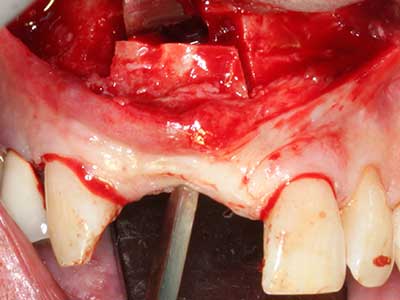

Fig. 2: Vertical and horizontal lateral maxillary defect with a high smile line with indication for pre-implant reconstruction.

Fig. 3: Basal separation of the block is easier with specially angled attachments.

Fig. 4: Additional autologous bone chips are harvested with the bone scaler.

Fig. 5: Checking the block size at the recipient site.